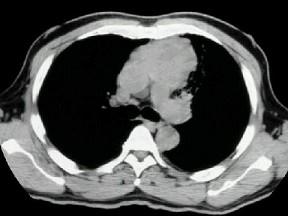

问题 男,26岁,自觉肌无力两周,胸片检查见纵隔增宽,CT检查如图,最可能的诊断为 ( )

选项 A、淋巴瘤侵犯血管 B、下纵隔畸胎瘤 C、胸内甲状腺瘤 D、中纵隔胸腺瘤侵犯血管 E、上纵隔畸胎瘤

答案 D